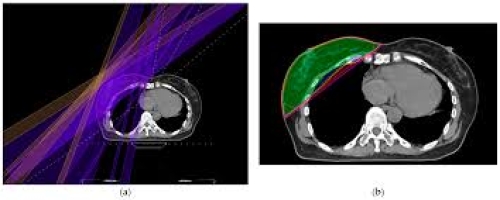

25 tháng 08, 2025Bài 3: Các kỹ thuật xạ trị hiện nay trong ung thư vú (3D-CRT, IMRT, Proton Therapy) Tìm hiểu chi tiết các kỹ thuật xạ trị ung thư vú: 3D-CRT, IMRT, proton therapy. So sánh ưu – nhược điểm, hiệu quả và lựa chọn ...Xem thêm